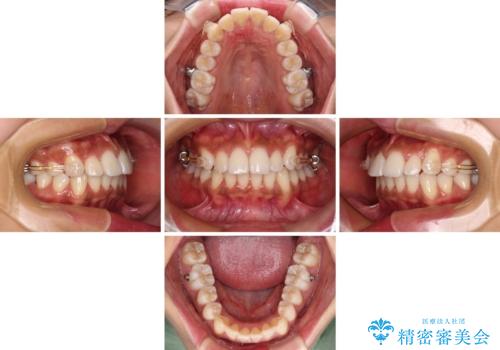

カリエール・ディスタライザーを併用したインビザライン矯正治療

インビザライン単体で改善することも可能ですが、ディープバイトのためインビザライン単体で達成する可能性が低いと考えられたため、カリエール・ディスタライザーという補助装置を併用して、より確実性を上げることとしました。

カリエールディスタライザーを併用したことで、確実かつ短期間で治療を終えることができました。